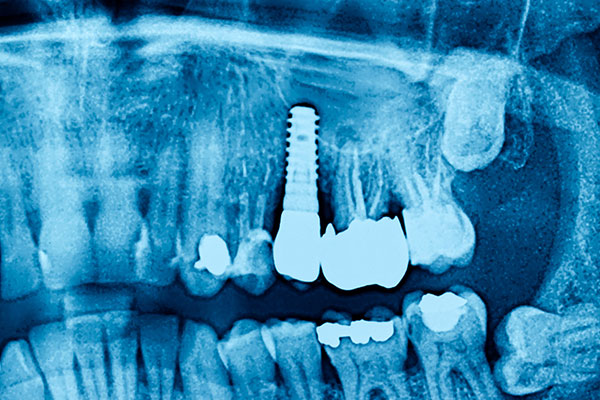

インプラント

当院では、歯を失った際にインプラント治療を行っています。これは、人工歯根を顎の骨に埋め込み、その上に人工の歯冠を装着する方法です。この治療により、天然の歯に近い見た目と機能を取り戻すことができます。インプラントは、ブリッジや入れ歯と比較して安定性が高く、隣接する健康な歯に負担をかけないため、長期的な口腔健康の維持に優れています。また、天然歯のような噛み心地を実感いただけるのも特徴です。当院ではインプラント専門医が歯科用CTを使用した精密な診断と、確かな技術で治療を行います。カウンセリングも承っておりますので、お気軽にご相談ください。